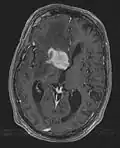

• MRI significantly underestimates extent of involvement; May appear focal on CT or MRI but parenchyma is typically diffusely involved.

• Intensely enhancing on MRI; may have a diffuse or “cotton wool” appearance on imaging.